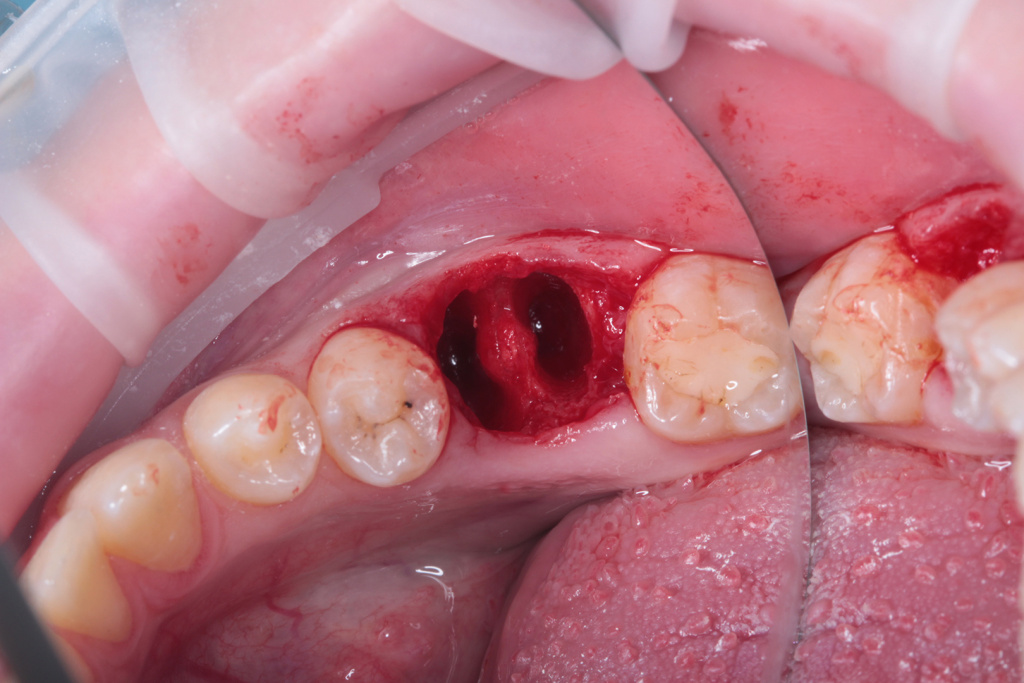

Удаление зуба 3.6